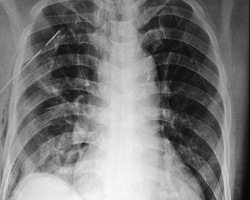

Како се поставља дијагноза спонтаног пнеумоторакса?

Диференцијална дијагноза: Мада је пнеумоторакс етиогенетски, клинички и РТГ добро познато патолошко стање, честе су погрешне дијагнозе или диференцијално дијагнозне заблуде. Тешкоће при препознавању спонтаног пнеумоторакса и других по клиничкој симптоматологији и морфолошком изгледу сличним плеуропулмоналних обољења, настају при малим физички тешко препознатљивим и РТГ уочљивим количинама ваздуха и течности у плеуралној дупљи. Разлог су и неуки физички и РТГ прегледи, погрешно тумачење клиничких симптома и знакова болести.